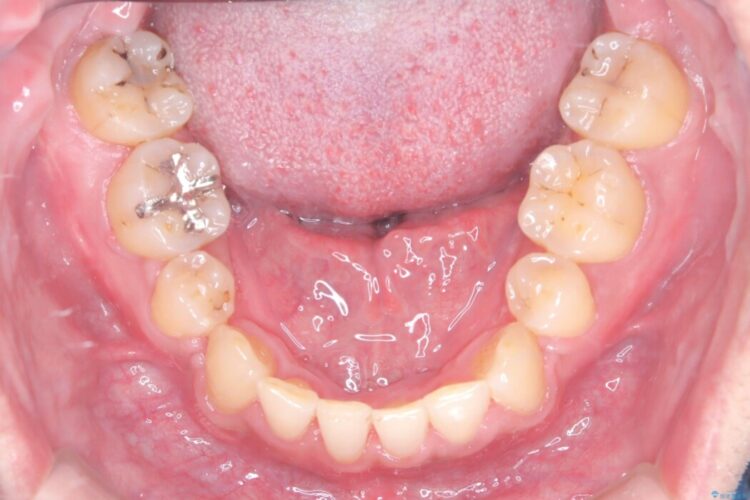

診査の結果、上下左右4番の歯を抜歯し、審美装置にて反対咬合と叢生を改善していくこととしました。

骨格性Ⅲ級を示しましたが、構成咬合位がとれたことから反対咬合と叢生改善のため、上下左右第一小臼歯を抜歯しワイヤー矯正を行いました。途中、バイトアップを行っています。